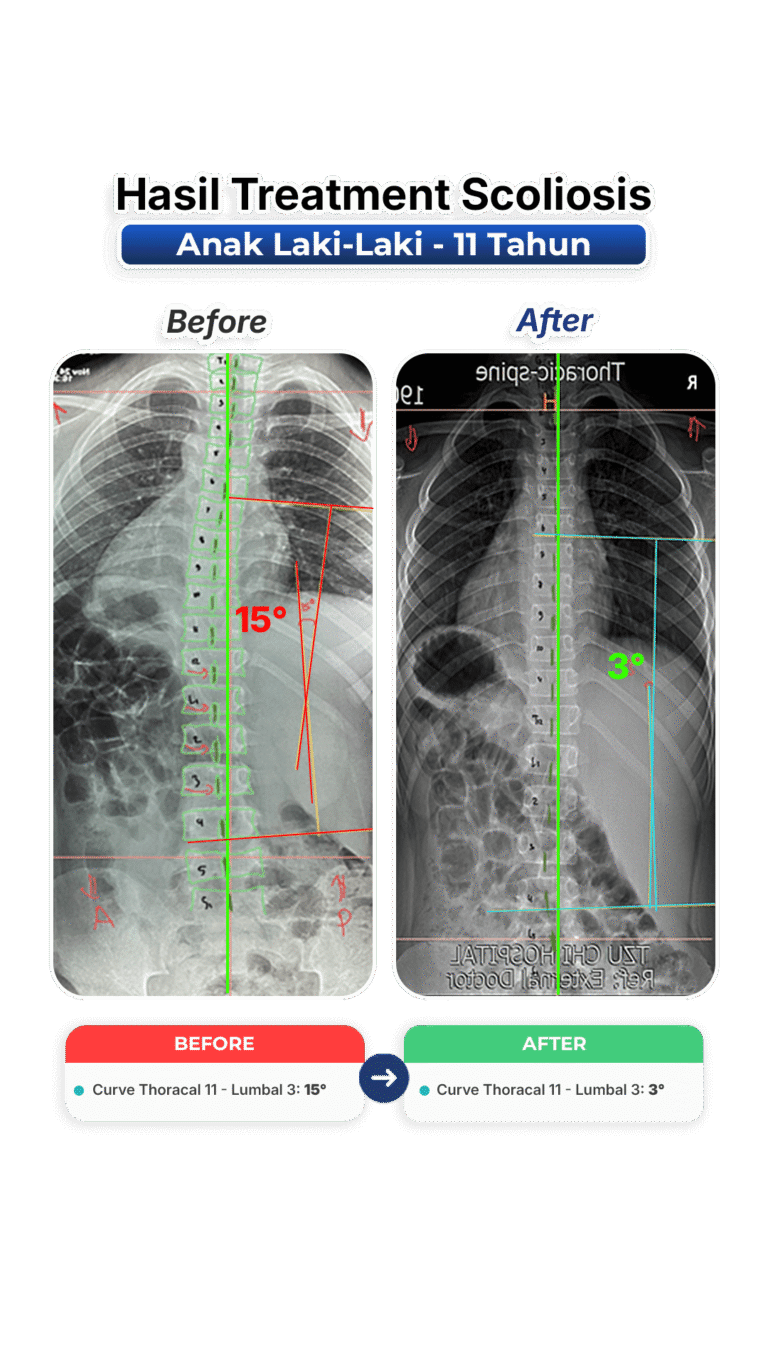

Perubahan nyata setelah mengikuti program terapi skoliosis di VLife Medical Galaxy Mall 3.

Perawatan scoliosis dilakukan melalui evaluasi tulang belakang menyeluruh, program terapi bertahap, fokus keseimbangan postur, mengurangi nyeri, memperlambat progres kelengkungan, serta meningkatkan fungsi gerak harian pasien secara aman dan terkontrol medis.

Penanganan skoliosis berbasis evaluasi postur menyeluruh, terapi manual khusus, latihan koreksi, serta pemantauan progres di setiap sesi. Dibuat untuk remaja dan dewasa yang ingin mengendalikan kelengkungan skoliosis dan mengurangi nyeri.